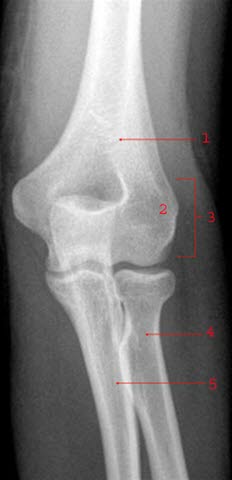

Gode røntgenbilder forutsetter at området som avbildes holdes i ro. Som regel er det nødvendig å ta bilder fra minst to retninger for å få en tilfredsstillende fremstilling av beinet. Vanligvis tas disse vinkelrett på hverandre - vanligvis forfra/bak og sidebilde (jfr. albue front og albue side nedenfor). Mer detaljert informasjon om et bein vil kunne kreve flere projeksjoner, f.eks. skråbilder.